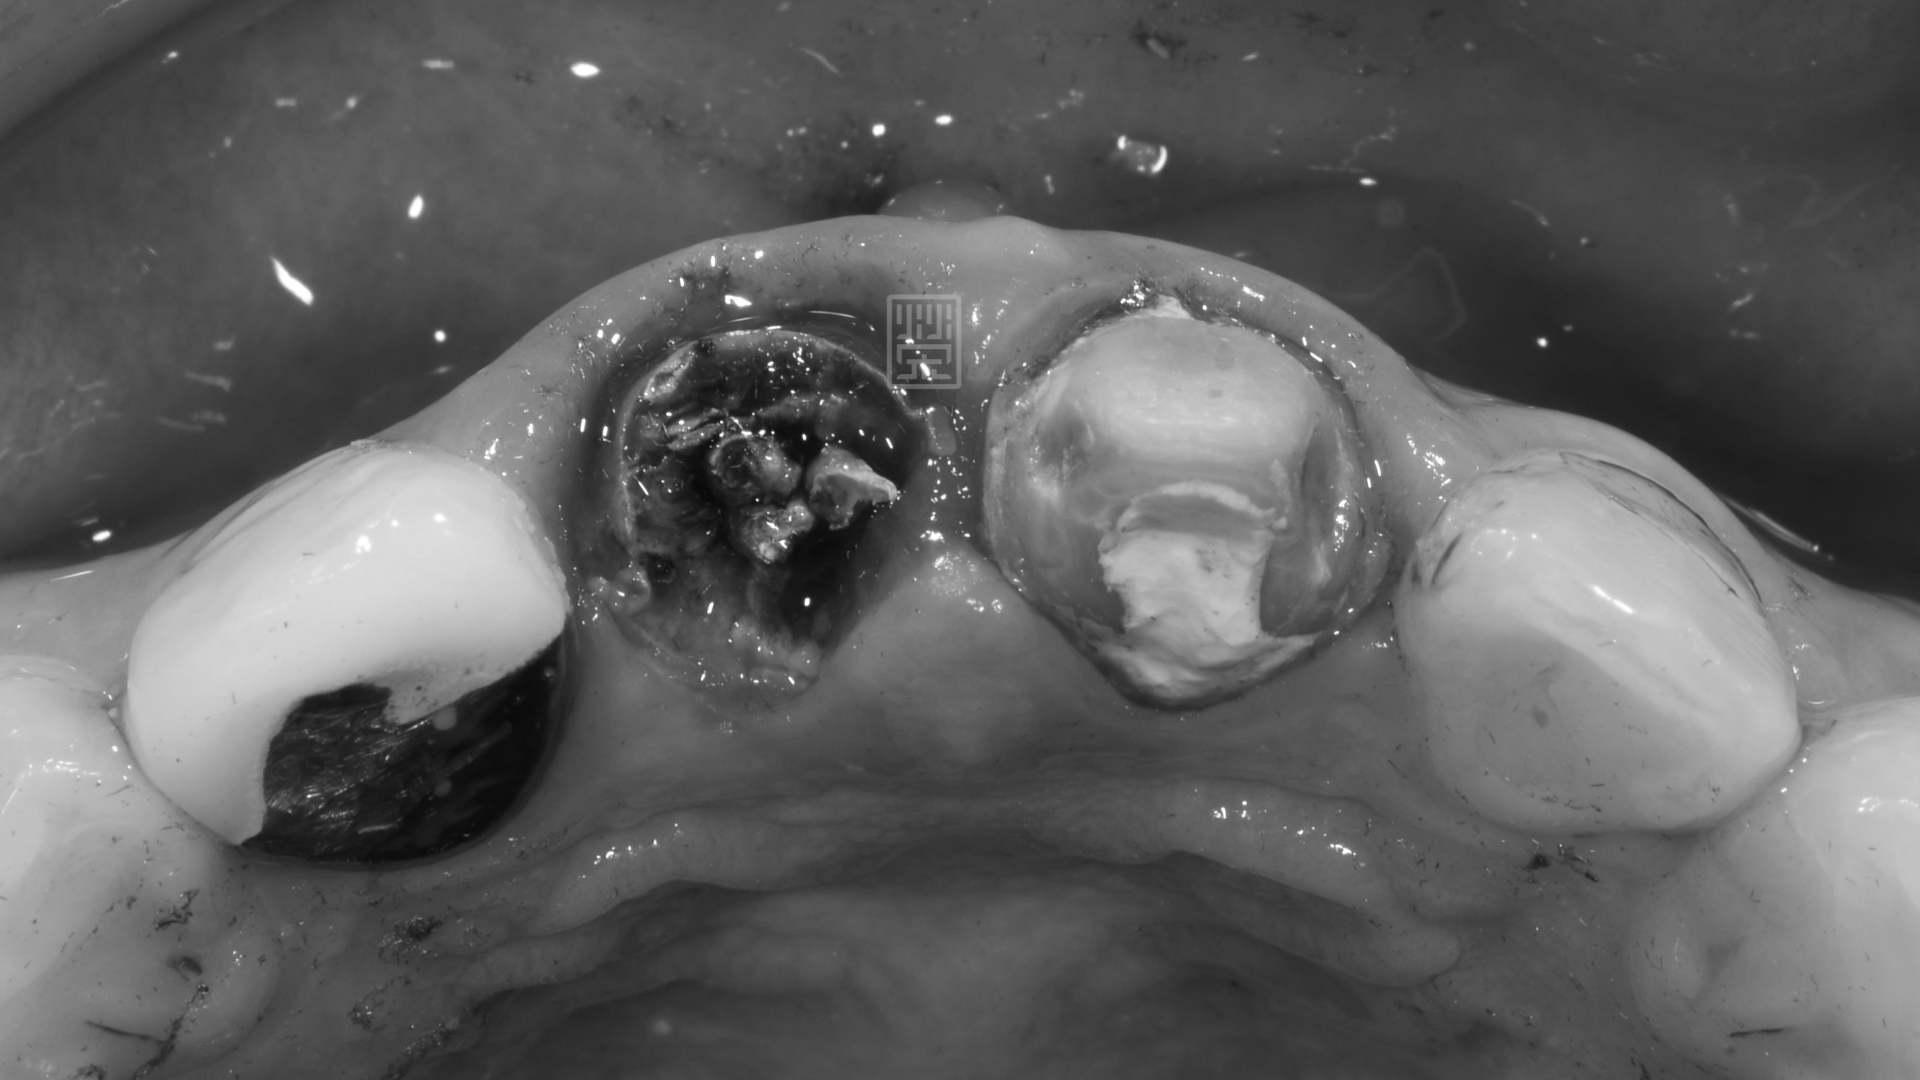

右邊門牙嚴重蛀牙